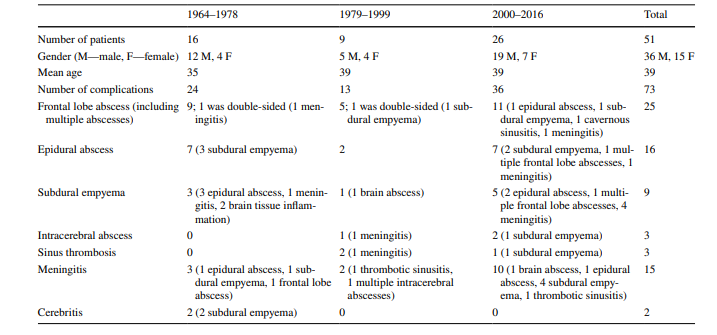

نتایج پنجاه و یک بیمار با عوارض داخل جمجمه ای سینوزیت از سال ۱۹۶۴ تا ۲۰۱۶ در این مطالعه وارد شدند. شرکت کنندگان از ۳۶ مرد و ۱۵ زن با میانگین سنی ۳۹ سال (یعنی محدوده ی سنی ۱۲ تا ۷۲ سال) تشکیل شده بودند. شیوع بیماری در بیماران با رده های سنی ۲۴-۲۵ سال بیشتر بود. جمعیت شرکت کننده در این مطالعه بسته به روش های درمانی متفاوتی که در طول دوره های زمانی ذکر شده ی قبلی ارائه شده، به ۳ گروه تقسیم شده بود: ۱۶ بیمار در دوره ی اول (۱۹۶۴–۱۹۷۸)، ۹ بیمار در دوره ی دوم (۱۹۷۹–۱۹۹۹) . ۲۶ بیمار در گروه آخر (۲۰۰۰-۲۰۱۶) قرار داشتند.

در ۲۵ بیمار، آبسه در سمت راست بود که شایع ترین عارضه ی یافت شده در تمام دورهها بود (۹ نفر در دوره ی اول، پنج مورد در دوره ی دوم و ۱۱ نفر در دوره ی سوم). تنها در یکی از بیماران مبتلا به آبسه ی لوب فرانتال چپ، آبسه های اپیدورال جمجمه و آمپیم ساب دورال وجود داشت. در بیمار دیگری، آبسه های فرانتال دو طرفه بودند. شانزده بیمار با آبسه ی اپیدورال (هفت، دو و هفت نفر به ترتیب در هر کدام از دوره های اول، دوم و آخر)، و نه بیمار با آمپیم ساب دورال (سه، یک و پنج نفر به ترتیب در هر کدام از دوره های اول، دوم و آخر) تشخیص داده شدند (شکل ۳).

در یکی از بیماران، چندین آبسه مغزی در لوب فرونتال و جداری مشاهده شد (شکل ۴). سه بیمار با ترومبوز سینوس علامت دار (۰، ۲ و ۱ در دوره های مربوطه) در کلینیک بستری شدند. دو بیمار سربریت داشتند. پانزده بیمار مبتلا به مننژیت بودند: هشت نفر با سبب شناسی استافیلوکوک یا استرپتوکوک و یک نفر هم با سبب شناسی ویروسی تشخیص داده شده. در دو بیمار، مایع مغزی نخاعی استریل بود (جدول ۲ و ۳).